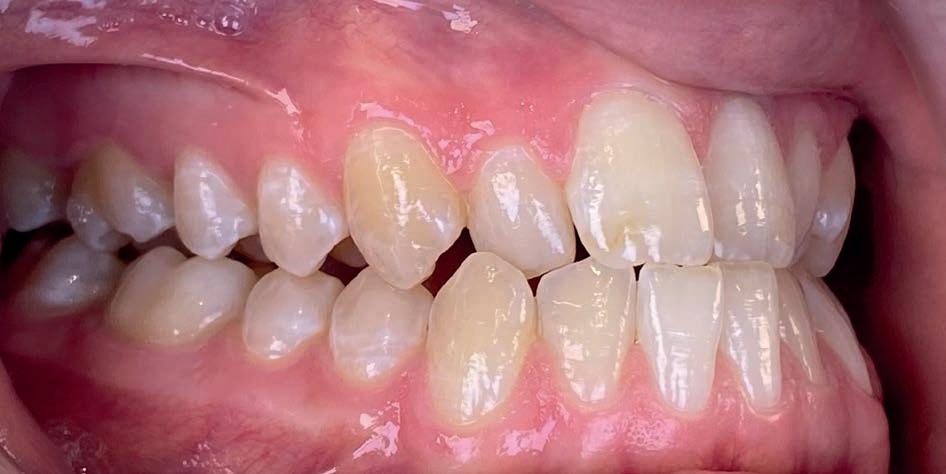

Casus in Proces

Patiënt Sonnie presenteerde zich met ernstig ruimtegebrek ter hoogte van de 13 en 44 en een kruisbeet aan de zijde van de 15 en 14. De 13 was ectostematisch gepositioneerd, waardoor extractie aanvankelijk als mogelijke behandeloptie werd overwogen.

Door een combinatie van verbreding en het inzetten van een D-gainer wordt de benodigde ruimte gecreeerd om alle elementen correct in de tandboog te positioneren, waardoor extracties kunnen worden vermeden. De behandeling zal binnen twee jaar worden afgerond; het eindresultaat wordt gedeeld in editie 2 van ons magazine.

Start behandeling

Midden behandeling

Laatste fase